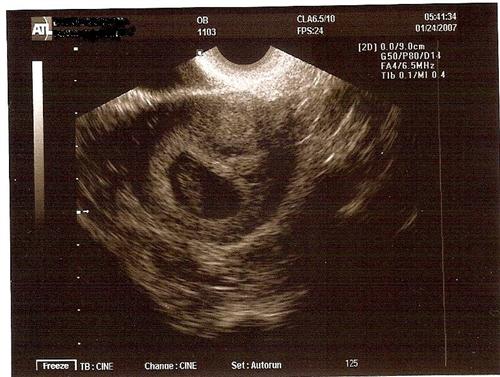

Just got back from the dr. Everything looks really good! The dr says that the baby was being shy and only wanted to show us its back! All the measurements look good! We saw the heartbeat- boy was it beating fast! It was soo good to see everything!

Here is a pic:

bump- pic is up!

Awesome pic. Congrats!

YAY LIZ!!!!!!!!!!!!!!!!!!!! Congrats on your peanut!!!!

aww look at the little peanut!